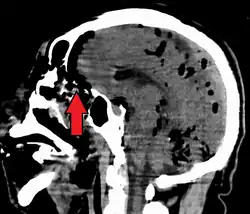

Pneumocephalus is the presence of air or gas within the cranial cavity. It is usually associated with disruption of the skull: after head and facial trauma, tumors of the skull base, after neurosurgery or otorhinolaryngology, and rarely, spontaneously. Pneumocephalus can occur in scuba diving, but is very rare in this context.

If there is a valve mechanism which allows air to enter the skull but prevents it from escaping, a tension pneumocephalus can occur (similar to what can happen in a tension pneumothorax).

CT scans of patients with a tension pneumocephalus typically show air that compresses the frontal lobes of the brain, which results in a tented appearance of the brain in the skull known as the Mount Fuji sign.[1][2][3] The name is derived from the resemblance of the brain to Mount Fuji in Japan, a volcano known for its symmetrical cone. In typical cases, there is a symmetrical depression near the midline (such as the crater of a volcano), due to intact bridging veins.[3] Its occurrence seems to be limited to tension pneumocephalus (not occurring in pneumocephalus without tension).[4] The sign was first described by a team of Japanese neurosurgeons.[5]